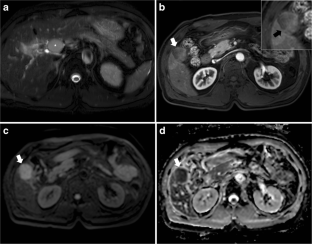

Fig. 1

Fig. 2

Fig. 3

Fig. 4

Fig. 5